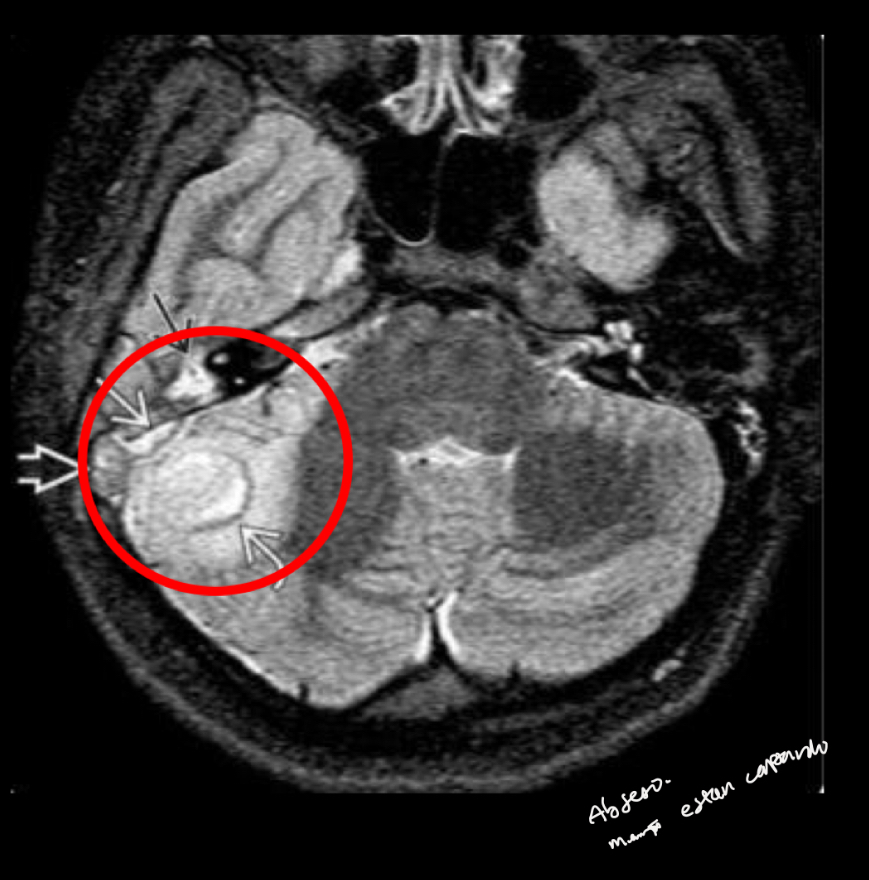

Q

Utilidad rm

A

ver extension intracraneal

en t2 q se ve

hiperseñal

Disminucion de señal en seno signoide

Capta contraste

como se ven los abscesos en tc opacificacion

pueden involucrar ECM(BEZOLD)

Pueden extenderse a fosa posterior y fosa craneal media